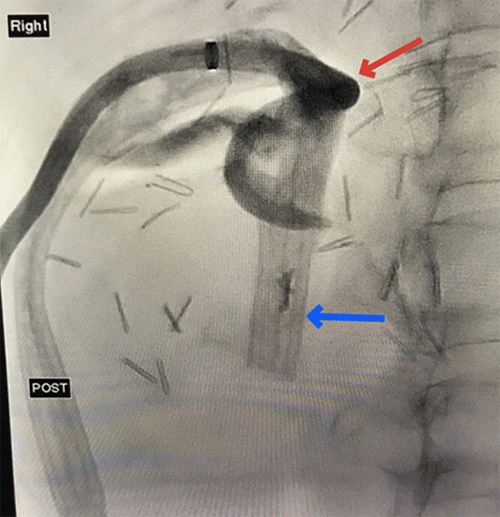

Following a discussion with the treating clinician and without practical alternatives, the drain was removed shortly after that. The microbiology, culture sensitivity specimen from the subhepatic space collection aspirate grew Enterococcus faecalis. Further percutaneous attempts were discussed with the interventional radiologist, who considered the collection inaccessible. On day 20 of the admission, due to persisting fevers, the subhepatic space collection was drained by endoscopic ultrasound, and a 4 cm pigtail catheter was inserted via the duodenum. The abscess cavity was noted to be approximately 4 cm from the duodenum and required transhepatic access. The procedure was uncomplicated, and subsequent imaging confirmed adequate positioning and reduction of the collection (Figure 3). The patient improved clinically, her closed suction drain was removed, and she was discharged to the hospital in the home program for outpatient intravenous antibiotics. She remains well on follow-up.

Figure 3. CT Abdomen and Pelvis Demonstrating Interval Improvement in Right Subphrenic Collection Post-Endoscopic Drainage with Plastic Stent In-Situ. Published with Permission